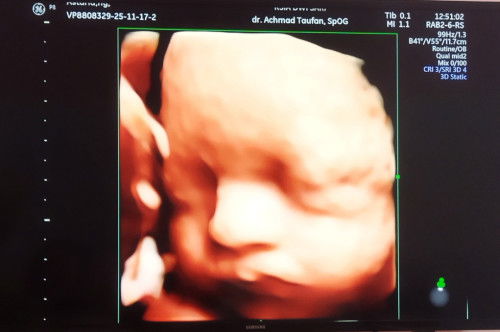

Usia kandungan 39 minggu